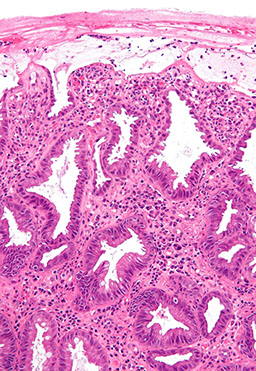

Histo of small bowel longitudinal sections

Duodenum

- difficult to tell GD junction on histo

- tissue subtypes:

1) mucosal/ antral/ pyloric type

2) villous absorptive type

3) transition btw other 2 types

- short fat villi

- highest conc of Brunner's glands (submucosal [vs intramucosal pyloric glands], cuboidal, light cytoplasm, tubuloalveolar glands, PAS-(+) cytoplasm, no goblet cells)

-- help to neutralize acid (?)